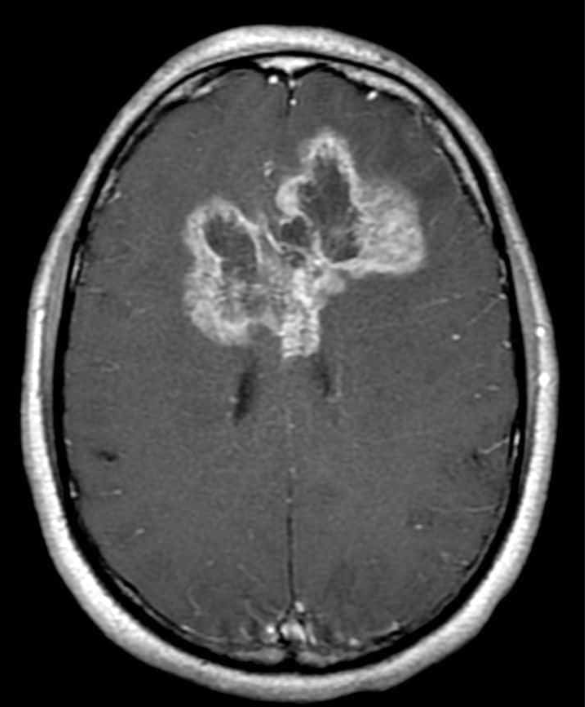

Glioblastomas have a tendency to spread across the corpus callosum, creating a bihemispheric lesion, sometimes described as resembling a butterfly.

The inner core of a GBM represents necrotic tissue. The outer, enhancing ring is made of hyper-vascularized tissue. GBM’s spread quickly, and are aggressive brain tumors with poor long term prognosis.

GBM’s often have a shaggy, contrast enhancing ring surrounding an area of central necrosis. There may be edema around the lesion. They may cross the corpus callosum, or extend into the brainstem.